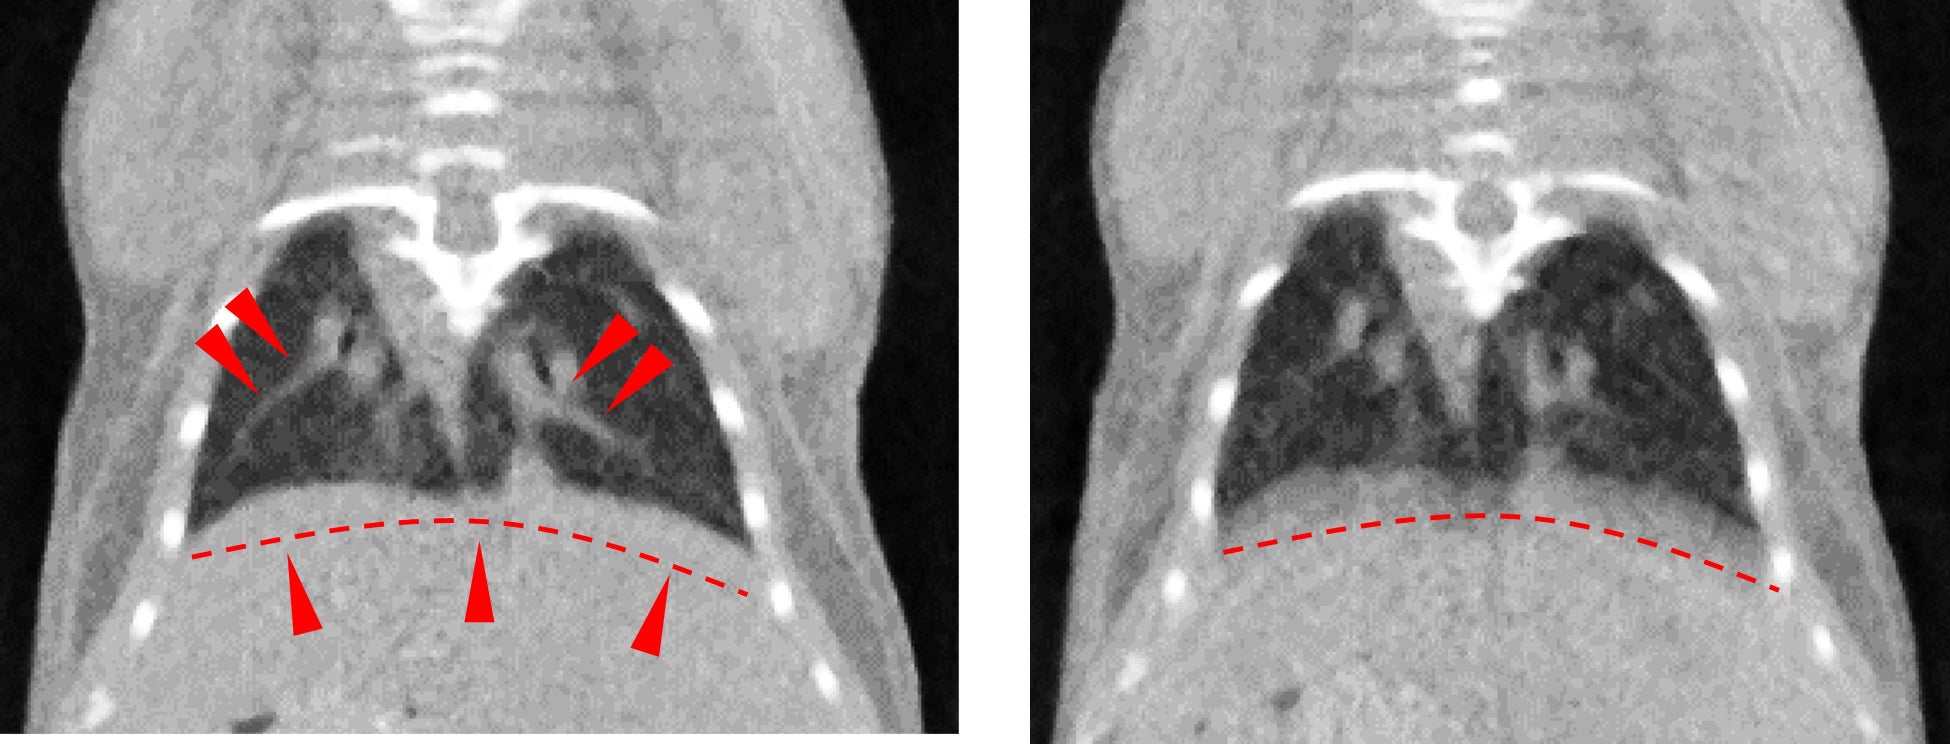

高効率&低被ばくで撮影ができる「息止めセンサー不要の呼吸同期X線CT」

従来の呼吸拍計などのセンサーを用いたCT同期撮影では、実際の呼吸に同期して撮影をするか、必要な投影角度のデータを収集するために複数回の撮影を行う必要がありました。

本技術は、CT撮影を行う際のX 線透過データから呼吸拍信号を抽出し、呼吸同期撮影を行います。これにより息止めや呼吸拍センサー無しで効率良く撮影することが可能です。また2回転撮影で呼吸同期データを収集できるため、複数回の撮影を行う必要がなく、短時間かつ低被ばくで呼吸同期CT撮影を行うことが可能です。本技術はX線CT装置「StellaScan」「CosmoScan」などに搭載されています。